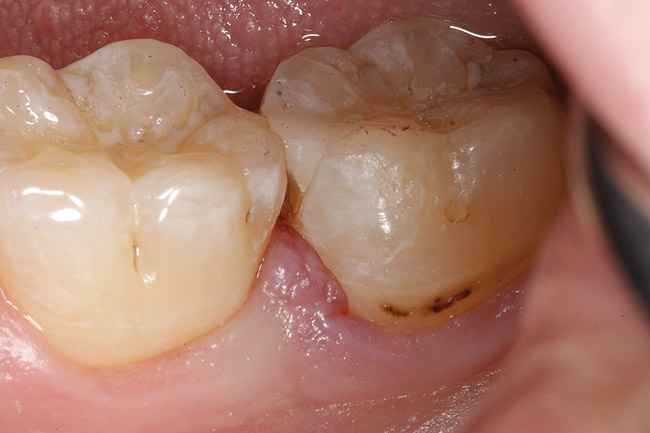

Fig. 5 Defective margins. Mandibular second molar with a Class II composite resin with a defective facial–gingival margin.

Figure 5  Defective margins. Mandibular second molar with a Class II composite resin with a defective facial–gingival margin.

Figure 5

Replacement of existing restorations is responsible for 75% of all operative dentistry.15,19 The reasons for placement and replacement of restorations of direct restorative materials include: primary caries (Figure 1 and Figure 2); recurrent caries (Figure 3); poor margins (Figure 4 and Figure 5); restoration fracture (Figure 6 and Figure 7); tooth fracture (Figure 8); esthetics (Figure 9); non-carious tooth structure lost (attrition, abrasion, abfraction, erosion) (Figure 10); and pain/sensitivity.